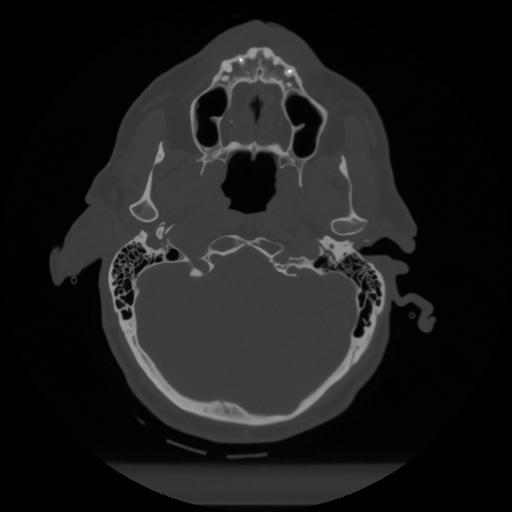

12 P.BLANDAS,,Vol,0.5,P.BLANDAS,,